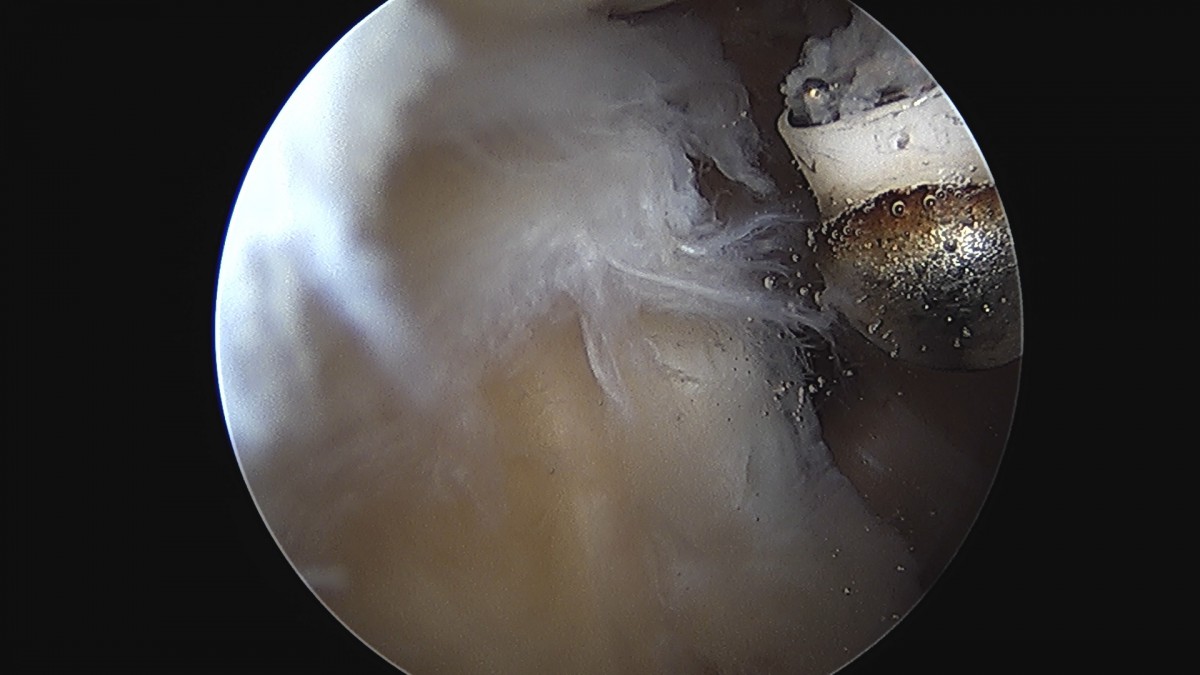

정지영원장님 어깨 회전근개 봉합술 임채O 환자

dae765e4d9ac96aee867c9d6292d8784_1758009112_4994.jpg

dae765e4d9ac96aee867c9d6292d8784_1758009113_1082.jpg

dae765e4d9ac96aee867c9d6292d8784_1758009113_696.jpg

dae765e4d9ac96aee867c9d6292d8784_1758009114_2696.jpg

dae765e4d9ac96aee867c9d6292d8784_1758009114_8496.jpg

dae765e4d9ac96aee867c9d6292d8784_1758009115_4361.jpg

dae765e4d9ac96aee867c9d6292d8784_1758009116_0151.jpg

dae765e4d9ac96aee867c9d6292d8784_1758009116_6072.jpg

dae765e4d9ac96aee867c9d6292d8784_1758009117_2049.jpg

dae765e4d9ac96aee867c9d6292d8784_1758009117_84.jpg